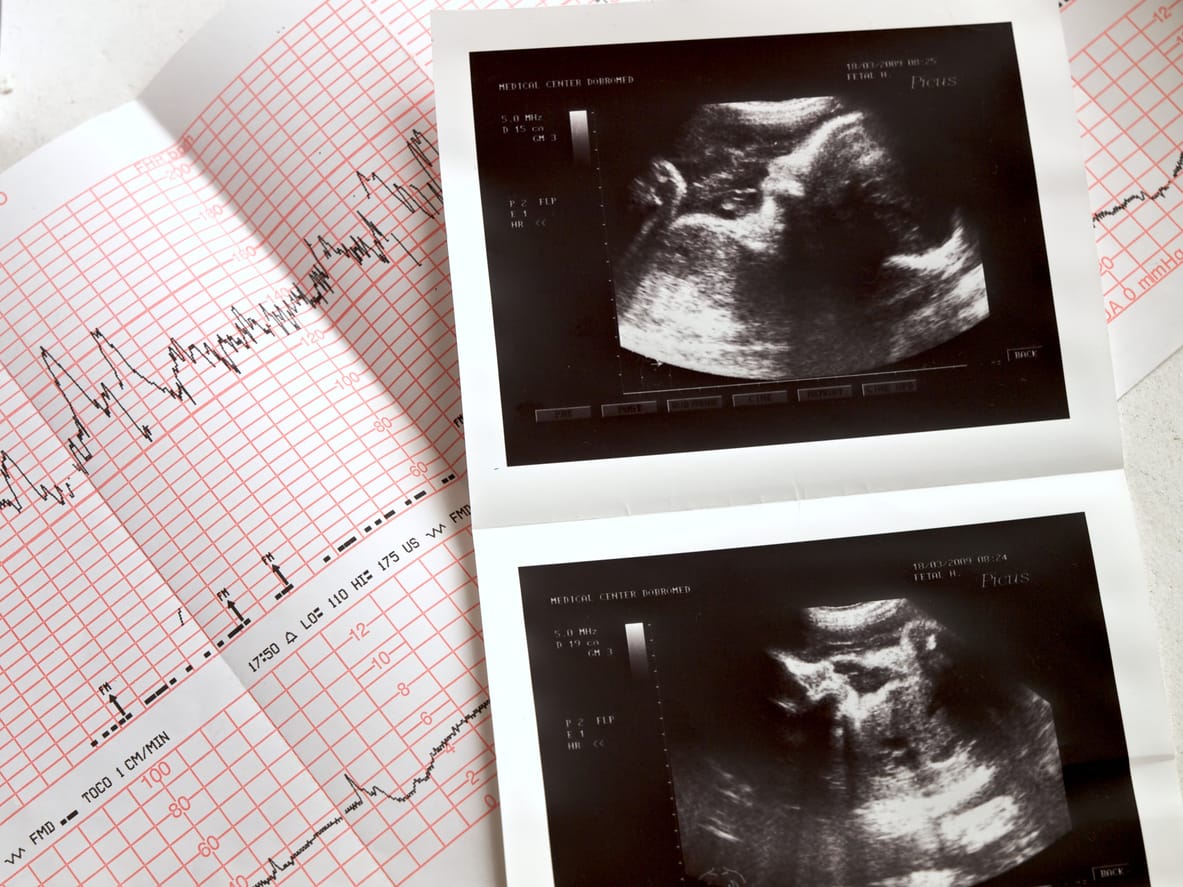

Although some effects of neurological damage will not be immediately apparent, low APGAR scores, abnormal blood-gas measurements and seizures within 12-24 hours tend indicate an asphyxic injury that can be confirmed by an MRI. Neurological damage from fetal distress and asphyxia may cause conditions such as Cerebral Palsy or severe mental and emotional impairment. In a matter of minutes, a newborn may sustain a birth injury that robs them of the opportunity to ever live independently. When a medical practitioner is negligent or incompetent in monitoring the fetal heartrate and it leads to a preventable a birth injury, you can take legal action. As one of the country's top personal injury firms, Gluckstein Lawyers understands what it takes to put together a strong case when making a claim of obstetrical malpractice. Using Auscultation charts, electronic fetal heartrate printouts and other health records in combination with professional guidelines and standards of practice, we can show that critical protocols were not followed and caused serious harm. With our firm's commitment to full-circle care, we are not only able to be your advocate you through the legal process, but also take a keen interest in learning how we can support you and your loved ones as you build a new life when the case concludes. To learn more about how our firm can help, contact us at [email protected].Did you miss Part 1 of this blog series?